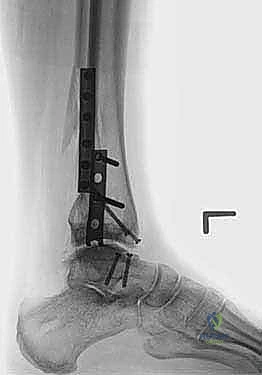

- في بعض الحالات المعقدة، قد يتطلب الأمر إجراء قص عظمي في الكعب (Malleolar Osteotomy) لفتح المفصل بالكامل ورؤية السطح المتضرر بوضوح، ثم يتم إعادة تثبيت هذا العظم لاحقاً.

4. زراعة الطعم وتثبيته (Graft Implantation and Fixation)

- يتم تشكيل الطعم المأخوذ من المتبرع ليطابق الحفرة التي تم إعدادها في كاحل المريض تماماً (مثل تركيب قطعة البازل).

- يتم إدخال الطعم برفق (Press-fit).

- لضمان الثبات التام، يتم تثبيت الطعم باستخدام براغي دقيقة جداً (غالباً تكون قابلة للامتصاص البيولوجي أو براغي تيتانيوم غاطسة تحت مستوى الغضروف حتى لا تحتك بالمفصل).

صور إضافية من داخل غرفة العمليات والخطوات الجراحية

ندرك أهمية توثيق الخطوات الجراحية لطلاب الطب والمرضى الراغبين في فهم دقة الإجراء. هذه الصور توضح مراحل زراعة وتثبيت الطعم العظمي الغضروفي بدقة متناهية تحت إشراف أ.د. محمد هطيف.